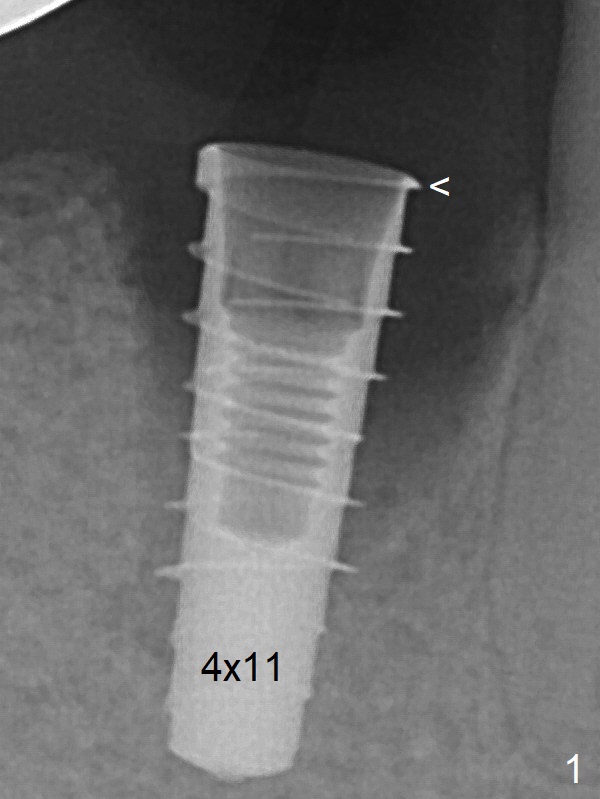

IBS种植体好像表面处理好,软硬组织愈合似乎很好,由于它使用五号钛合金,比四号钛合金硬(三倍),不容易断裂,所以毫米种植体用于狭窄的磨牙区仿佛没有问题,而绝大多数种植体使用四号钛合金。